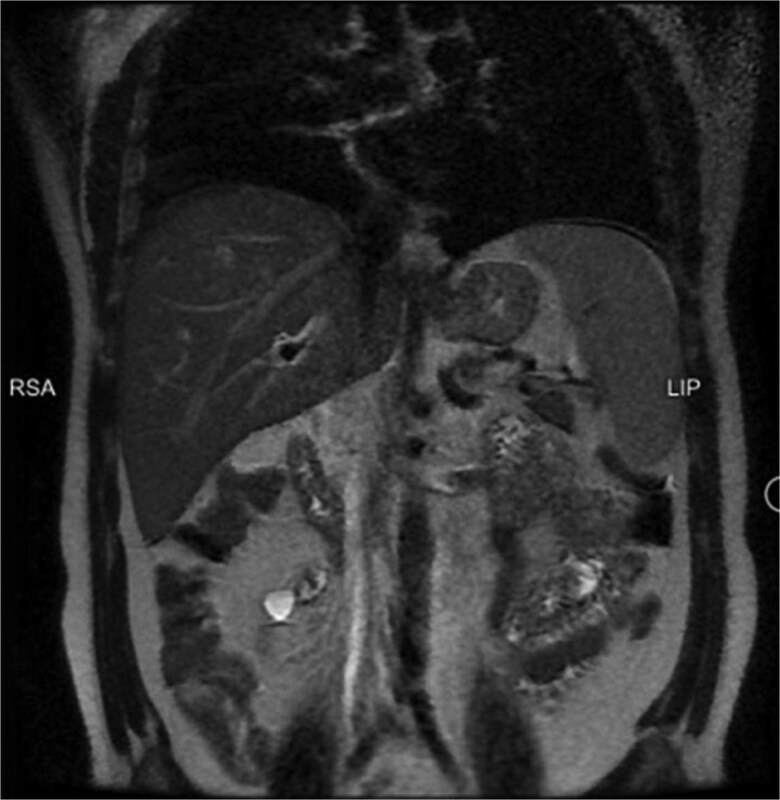

Abstract Image